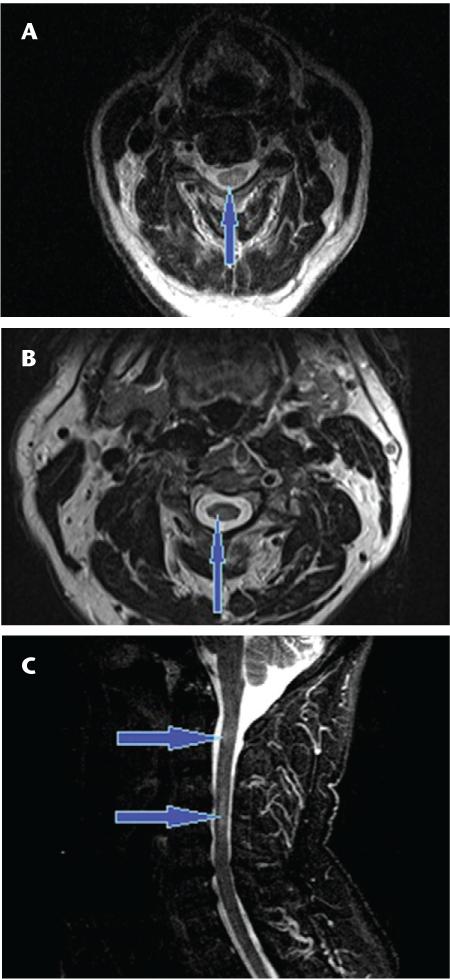

Long-segment linear T2-hyperintense lesions in the spinal cord have been shown to be characteristic of NMO myelopathy.16 17 Additionally, in our experience the typical lesions are symmetrical and centrally located in the cord (Figures 1 and 2). Those seen in MS myelopathies are usually less extensive on cross-sectional imaging and are typically asymmetrical and located at or near the periphery of the cord (Figure 3).

Axial T2 fast spin echo (A, B) and sagittal short tau inversion recovery (STIR) (C) sequences showing the typical peripheral signal changes on axial images (A, B) and discontinuous high T2 signal (arrows) involving short segments of the spinal cord (C) in a patient with multiple sclerosis